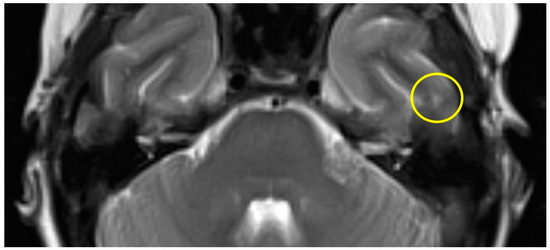

| slight (1) | parts of the inferior temporal gyrus, less than half of the thickness (cranial-caudal) |

| Patient #1 | T2 | f | 58 | left | 12 months | 175 min | slight |

| Patient #2 | T2 | f | 62 | right | 16 months | 159 min | slight |

| Patient #3 | T2 | f | 57 | left | 11 months | 131 min | slight |

| Patient #4 | T1 | f | 49 | left | 12 months | 159 min | slight |